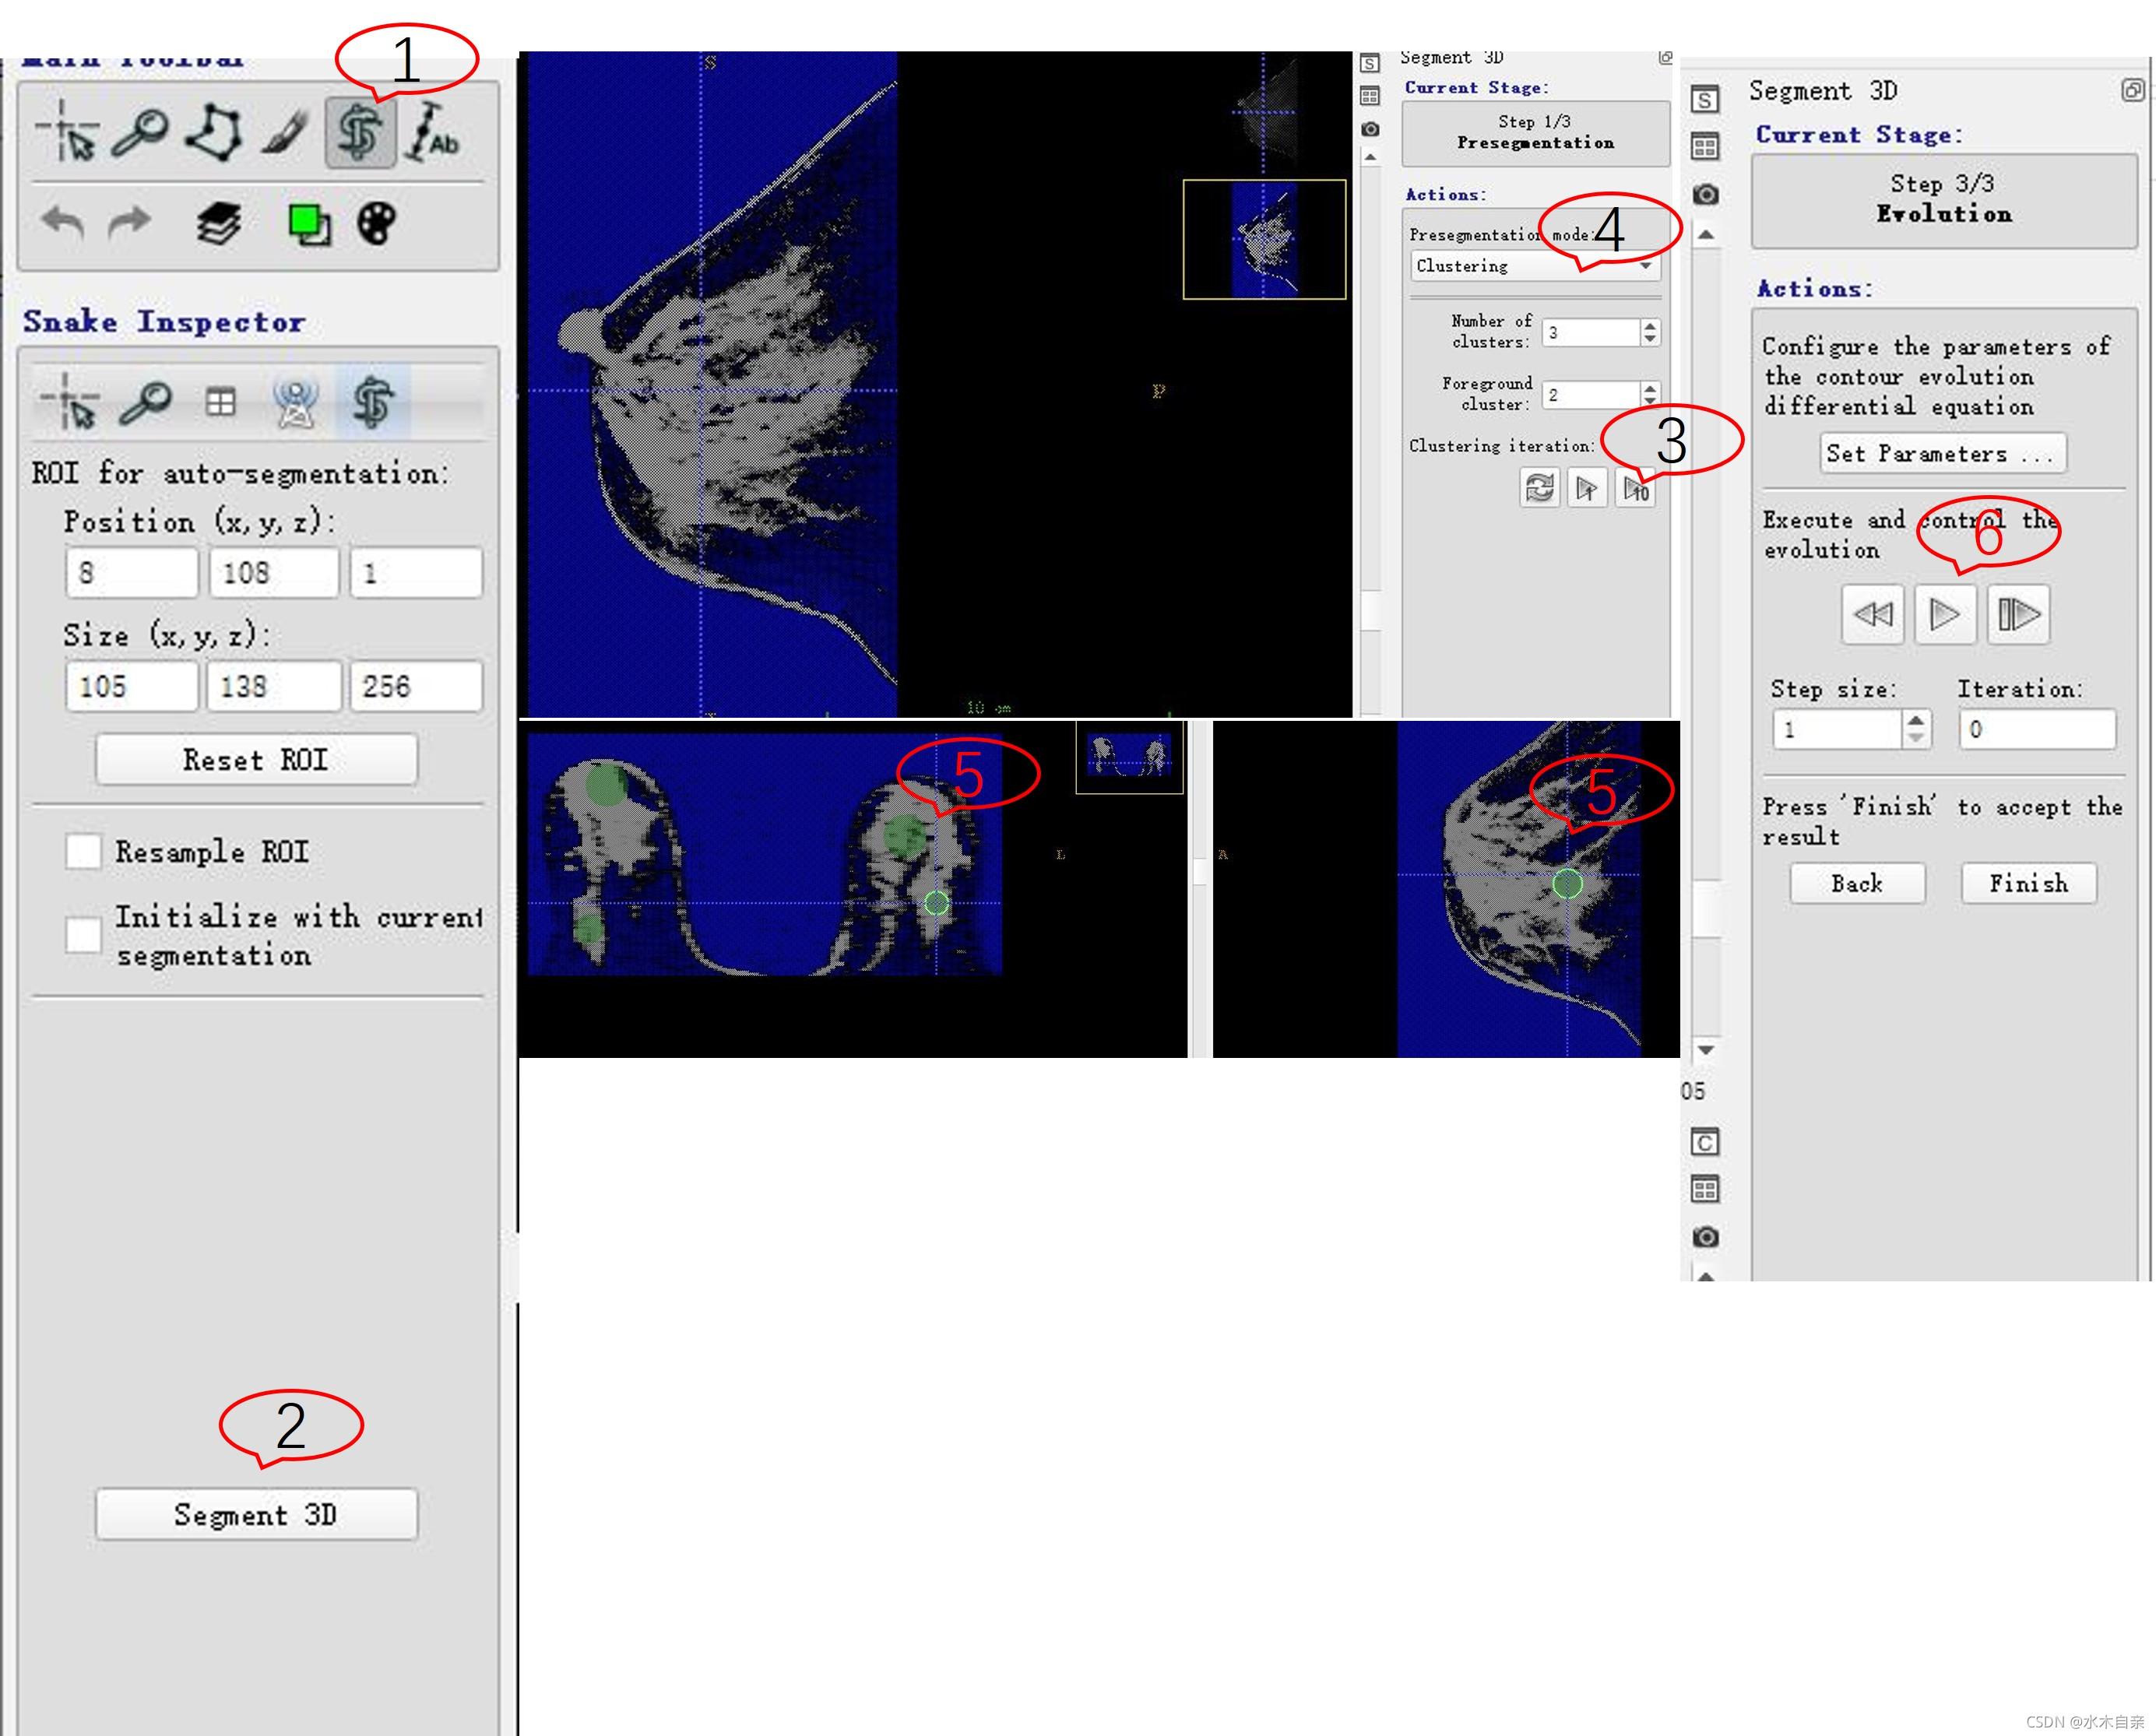

1 选择蛇形按钮,在轴位、矢状位、冠状位调整欲分割的区域,包括乳腺。

2 点击“Segemnt 3D按钮”,进入自动分割区域。

3 选择欲采用的分割算法,针对动态增强序列,笔者尝试了Thresholding、Classification、Clustering、Edge Attraction几种方案,对于动态增强序列,以Clustering最优,其它序列可以尝试其它方法。

4 点击优化按钮进行分类优化,对腺体进行分割,首先选择该组织组织对应的类别,本例为“2”,点击next

5 添加种子点,尽量均匀可以连通到欲分割额组织全部,如图所示。

6 点击“迭代”按钮进行迭代。达到效果的时候点击完成。可以结合手动分割功能进行微调。

图示步骤:

注:步骤3为选了了“clustering”之后进行优化结果,步骤4 为查看该方法的最终效果,与其它方法进行比较而点击;步骤5位设置种子点,可以设置多个,并注意调整适当的大小,使之腺体在多个种子点的作用下成为一个准确的连通区域。